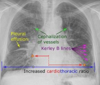

3

4

5

A: edema alveolar B: líneas B de Kerley C: cardiomegalia D: dilatación de vasos en lóbulos superiores E: derrame pleural

130

Insuficiencia cardiaca